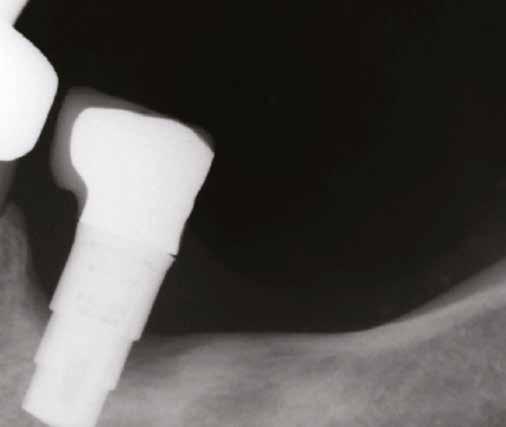

1. ábra: Dr. Jung 10 éves kontrollal rendelkező 4.7-es helyén levő Dentium short implantációja. Preoperativ CT, ínyformázó 4 hónappal a műtét után, valamint 4 hónap múlva 4.7-es szólókorona.

Prof. Jung Ui Won szöuli parodontológus a rövid implantátumok rizikómenedzselésével foglalkozott előadásában. Eseteket mutatott be 10 éves követéssel, ahol rendkívül alacsony csontkínálat mellett tudott sikeresen short megoldást találni.